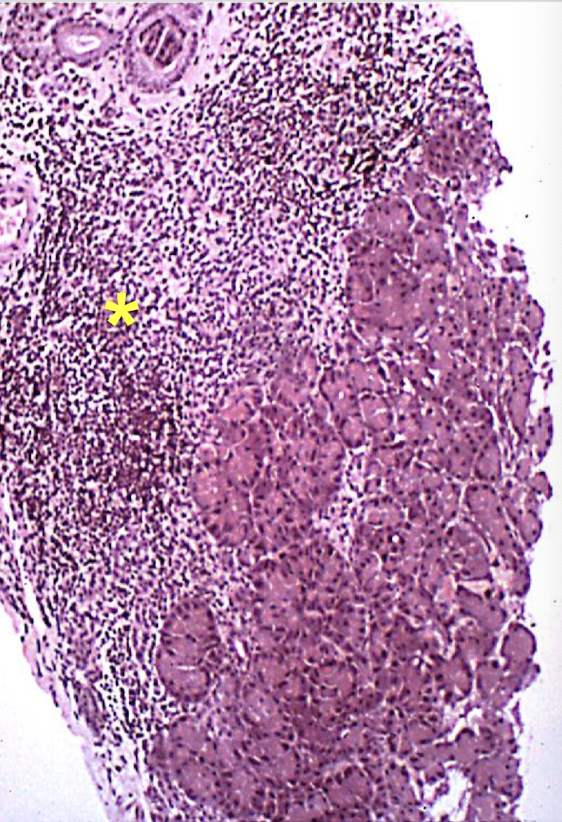

What is grossly seen in severe cases of acute pancreatic necrosis in dogs?

hemorrhagic pancreas w prominent edema & multi-colored areas

chalky white areas of fat necrosis by lipolytic enzymes (w 2o mineralization)

What is seen in addition to necrosis of acinar tissue, neutrophils, & fat necrosis in dogs with acute pancreatic necrosis?

calicum deposits in saponified fats → peripancreatic fat necrosis